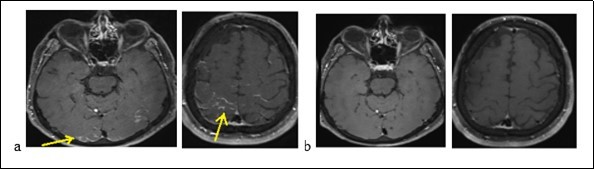

Mr. P.B., a man of 56, suffering from a left sudden hemiparesis within 30 minutes, was admitted to hospital on September 21, 2017. The beginning was marked by a feeling of head emptiness and unusual serious headache during a flight. This headache was followed by gradual paraesthesia of the left hemibody, moving from the vertex to the lower limbs. A left hemiparesis and speech disturbance resulted from paraesthesias. These symptoms decreased about 10 minutes. The plane had landed under an emergency condition and the patient was admitted to stroke emergency unity. There is a need to say that he had no history of vascular pathology before. On test, the result showed that blood pressure was 144/96 mm Hg. Consciousness of the patient was normal with good temporo-spatial orientation. Besides, Neurological test and other tools were normal. The routine biological test was normal too: the blood count, the C-reative Protein (CRP), blood urea, creatinine, ionogram, transaminases and gammaglutamyl transferases were normal. There was no abnomalies in the immunological assessment (antinuclear, anti cardiolipids, anti B2 GP1, circulating anti-body of lupus type, ANCA and native anti DNA). The serologies: Human immunodeficiency virus (HIV), Syphilis, Lyme, viral hepatitis C and B (HVC, HVB ) were negative. The cerebro-spinal fluid (CSF) was normal. A brain MRI (Figure 1a) displayed a cortical contrast enhancement in relation with possibly pial leptomeningeal involvement, some hypersignals on Flair sequences of frontal and parietal subcortical white matter. An assessment of pachymeningitis with a thoraco-abdomino-pelvic scanner and an electroencephalogram (EEG) were normal. The cerebral MRI (Figure 1b) after 8 days had shown a complete regression of the lesions. We noted that the diagnosis of an RPE syndrome facing the serious onset of symptoms, the MRI findings and the complete decrease of the lesions.

Figure 1.Brain MRI displaying occipital cortical hypersignals in Flair sequences (a) and decrease of lesions (b)